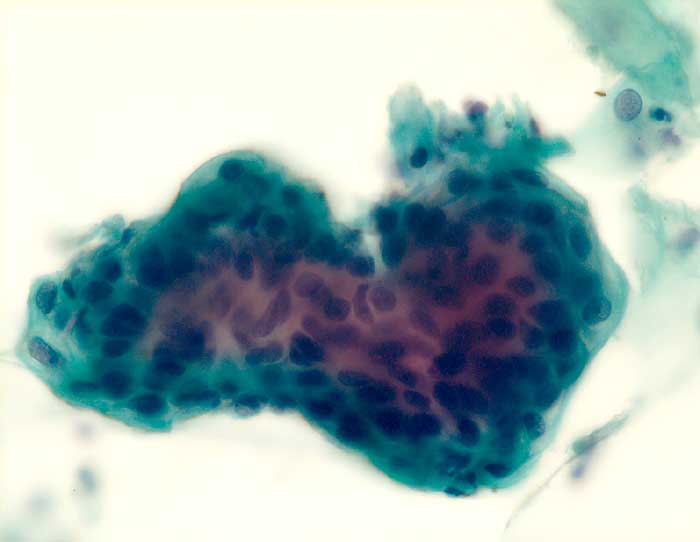

PathoPic ID 6071 - Endometrium

Endometrium

Normalbefund

Portio

Genitalorgane, weiblich

Portio: Endometriumzellverband

Postmenopausenblutung

Zytologie

500

75